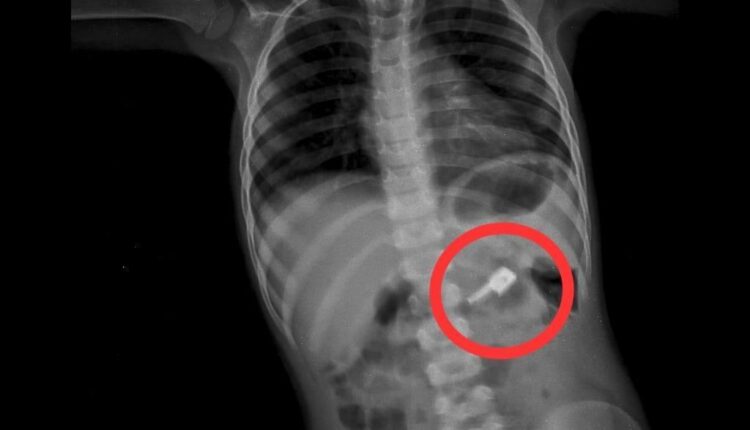

В приемный покой детской больницы обратилась мать с жалобой, что ребенок 3 лет проглотил бегунок от застежки «молния» на одежде. Маленького пациента лечили заместители главного врача Чинибеков Сейдахмет Байдуллаевич и Кенжалы Маулим Казиевич. В диагностике инородных тел желудочно-кишечного тракта наряду с тщательно собранным анамнезом большое значение имеет динамическое рентгенологическое исследование. Так, на обзорной рентгенограмме брюшной полости были обнаружены бегунок и предположительно две швейные иглы в проекции желудка. При проведении процедуры ЭФГДС из желудка удалена одна игла, бегунок отсутствовал.

— На контрольной R–грамме брюшной полости обнаружены еще 2 иглы в верхнем этапе брюшной полости и 1 игла в проекции таза. Проведена повторная ЭФГДС и удалена игла из желудка. Затем при помощи колоноскопии удалена игла, фиксированная в сигмовидной кишке, — сообщил Сейдахмет Байдуллаевич, врач-хирург высшей категории.

Ребенок продолжал находиться под наблюдением. На контрольной R–грамме брюшной полости обнаружена четвертая игла в проекции таза. Проведена колоноскопия и из сигмовидной кишки удалена последня игла, которая концом была фиксирована в слизистую кишечника. В настоящее время ребенок в удовлетворительном состоянии выписан домой.